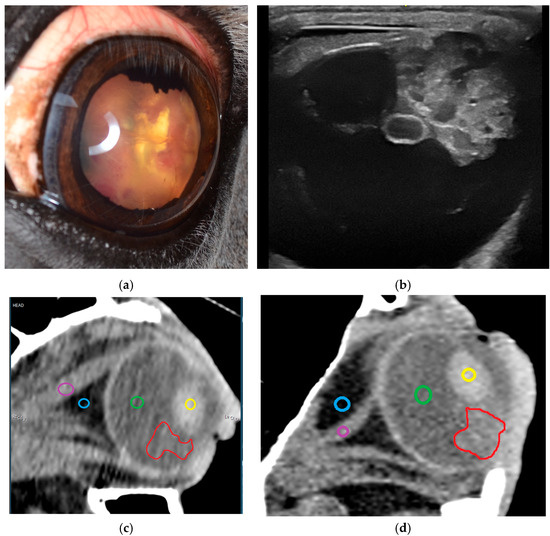

Intraocular Tumors in Horses: Diagnosis, Tumor Classification, Oncologic Assessment and Therapy

Intraocular neoplasia in horses is rare and only few case reports and small case series exist. Intraocular neoplasia has various clinical signs and includes important differential diagnoses in ocular disease. This narrative review of the current literature aims to provide a clinically relevant overview and classification of intraocular tumors in horses and adds a comparative oncological perspective concerning diagnosis, treatment and future considerations. The available clinical and imaging examination techniques allow for a reliable and differentiated investigation of the tumor, even in the standing horse, using high-frequency ultrasound or optical coherence tomography, which have gained importance in equine ophthalmology. Sectional imaging techniques, in particular computed tomography, are suitable for the examination of the peribulbar, retrobulbar and orbital structures. Differentiated diagnostics including precise tumor staging (TNM: tumor, node, metastasis) are essential for a general prognostic and therapeutic assessment. The embryologic and anatomic tissue origin of the neoplasm is the basis for clinicopathologic classification. Medulloepithelioma and uveal melanocytic neoplasia are the most common intraocular tissue formations occurring in horses. Whereas melanocytic neoplasia of the iris can be treated surgically, neuroepithelial tumors regularly lead to bulbus extirpation. Other primary intraocular neoplasms are sporadically reported, as well as intraocular metastasis of systemic neoplasia. Chemotherapy and radiation therapy are not currently used to treat intraocular neoplasia in horses and need to be further investigated, especially regarding the latest developments in human and small animal medicine. In addition, horses and dogs may serve as models for human oncologic research. Full article

Show Figures

Figure 1